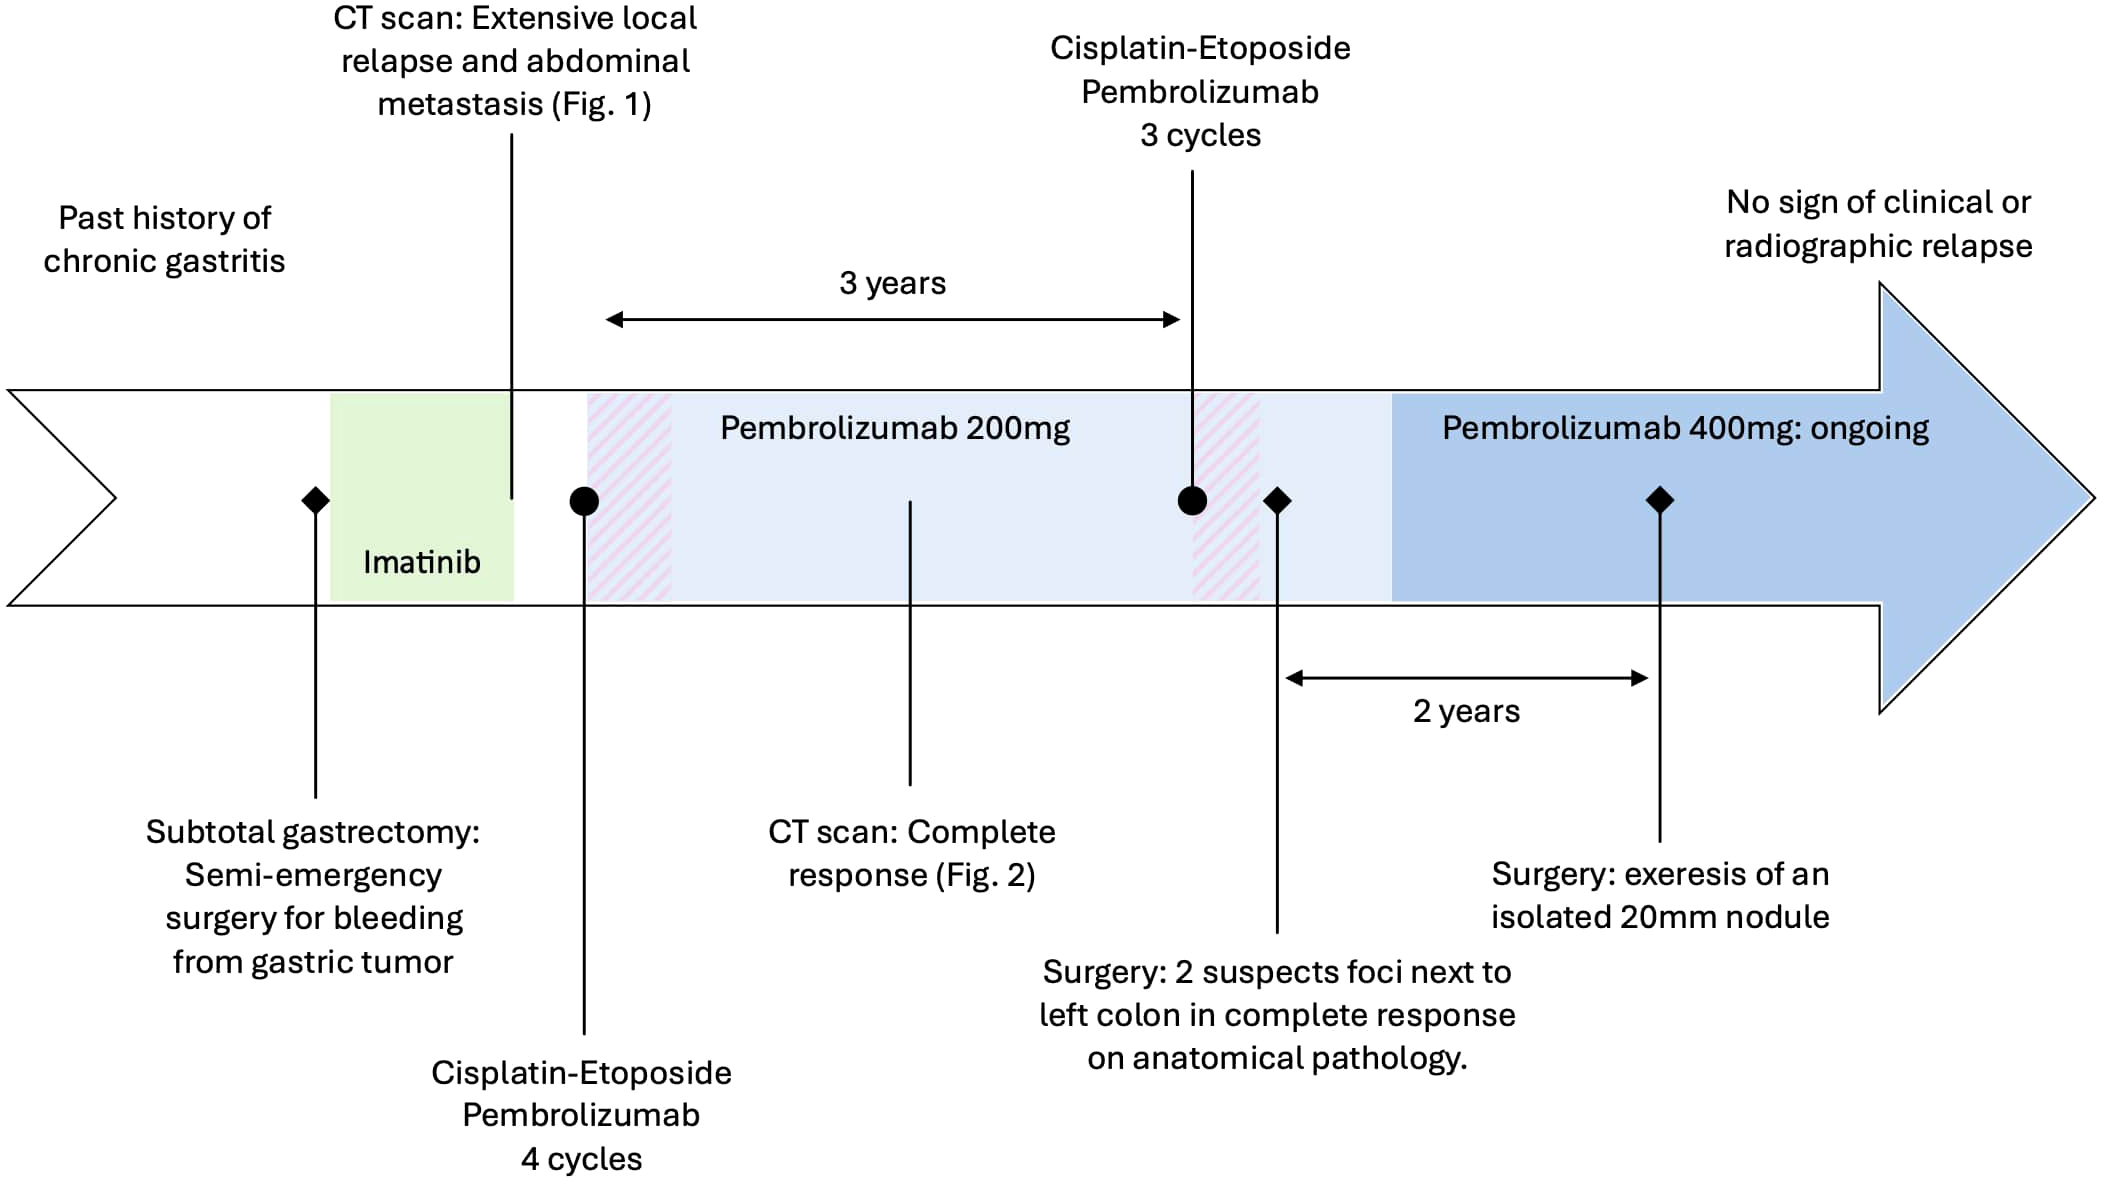

Two years later, an isolated hypermetabolic 16 mm para-gastric focus was detected on PET scan. The nodule was removed, showing recurrence of an SDH-deficient GIST. A consultation at a national reference center proposes a continuing immunotherapy treatment of intravenous pembrolizumab 400 mg and close radiologic and clinical monitoring. The RET gene fusion may be activated in the event of relapse. To date, the patient has no functional limitations and is asymptomatic, with no radiographic relapse (Figure 3).

Figure 3

Patient timeline with relevant data from the episode of care.